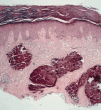

También puede ocurrir en asociación con múltiples neoplasias, benignas y malignas, apareciendo habitualmente en el tejido que rodea al tumor. Entre las primeras destaca el pilomatricoma (Fig. 1), que en el 75% de los casos aparece calcificado; en los pilomatricomas perforantes puede ocasionalmente verse la eliminación de material cálcico a través del tumor mediante un proceso de eliminación transepidérmica, posiblemente originado en la masa tumoral que actuaría como cuerpo extraño (9). Entre las malignas, en un estudio de 200 carcinomas basocelulares 41 casos (21%) mostraron evidencias de calcificación distrófica, en contraste con seis casos (3%) en carcinomas espinocelulares; los basocelulares calcificados mostraron un subtipo histológico más agresivo y tendían a localizarse en el tronco (10).

FIG. 1.--Pilomatricoma. Lesión de consistencia dura, lobulada y de coloración amarillenta.